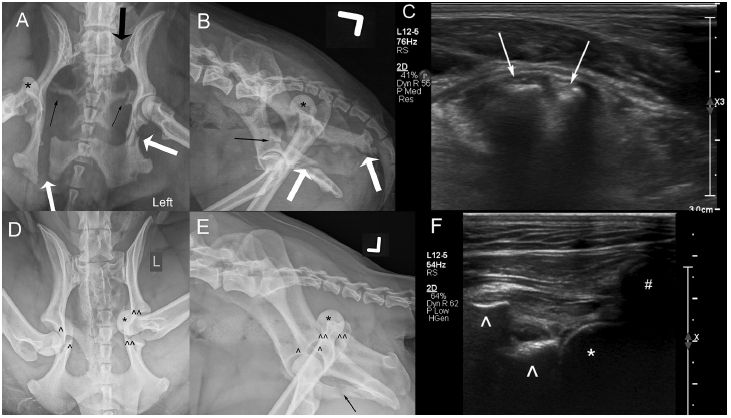

CSCU Assisted Pub: Ultrasound is an accurate imaging modality for diagnosing hip luxation in dogs presenting with hind limb lameness doi.org/10.2460/javm...

Congratulations! @research-and-innovation.cornell.edu @cornellvet.bsky.social